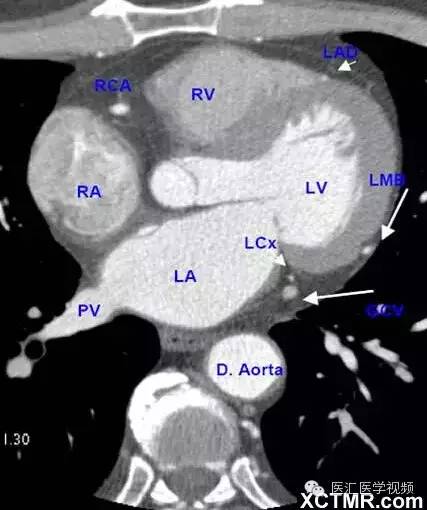

带你全面了解心脏冠状动脉ct解剖

主动脉根部层面ct和mri断层解剖

影像解剖|心脏冠状动脉ct解剖中文详细标注(图文)

所属相册:心脏冠状动脉ct解剖中文详细标注(图文 cardiac a所属相册

超全总结心脏ct解剖图谱